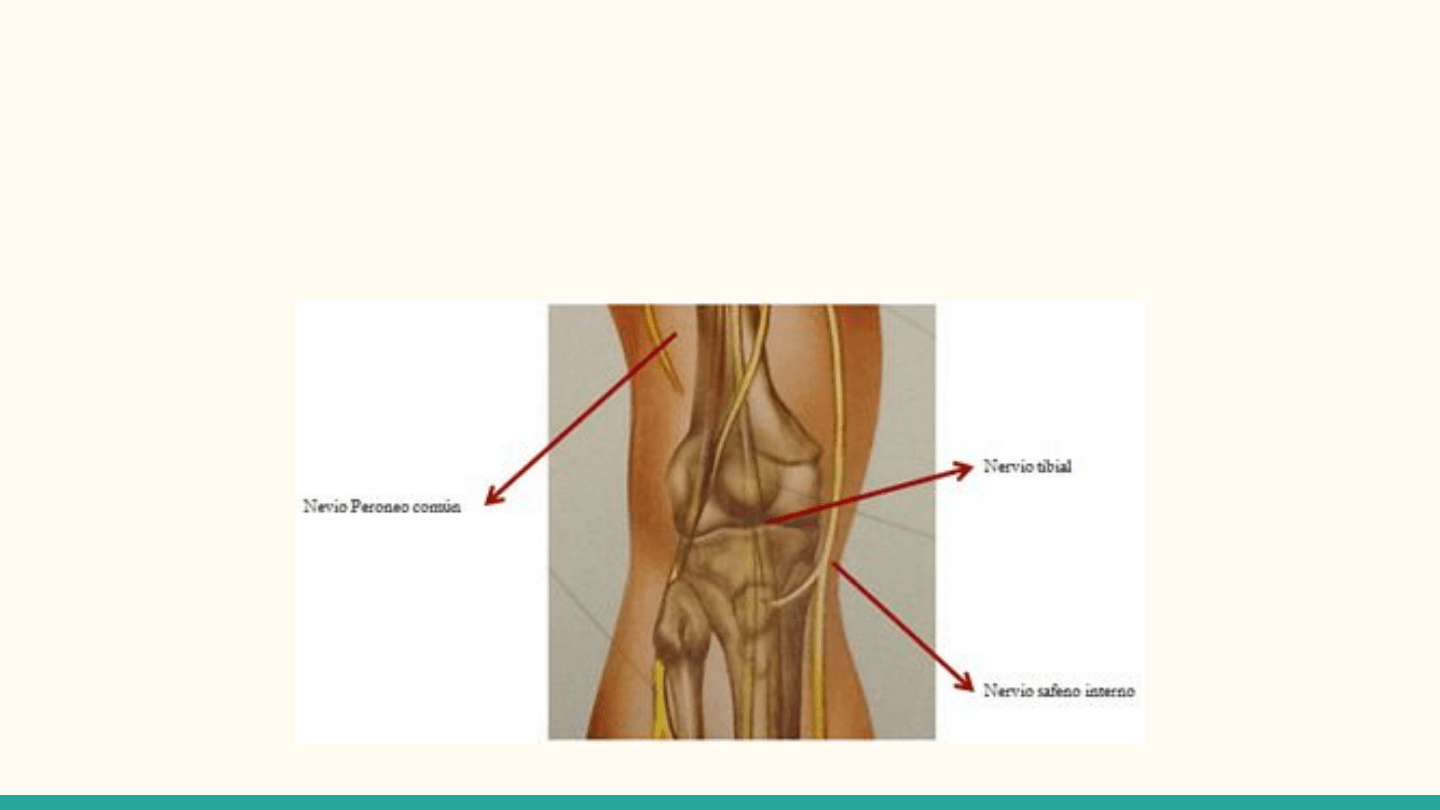

Ramos articulares de los nervios femoral, tibial y fibular

(peroneo) común

Nervios (cutáneos) obturador y safeno